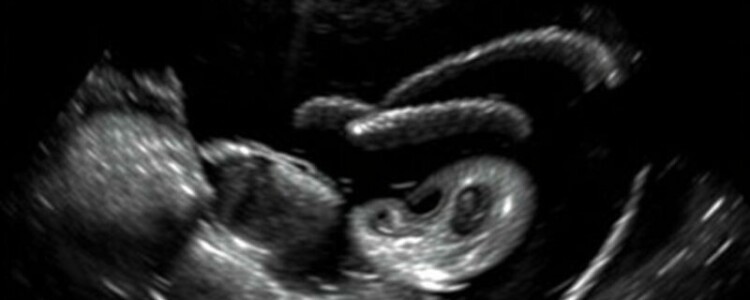

Vesícula biliar y vías biliares

La sonografía es la técnica de elección para sospecha de colecistitis: signos como cálculos impactados, engrosamiento de la pared >3 mm, signo del murphy sonográfico (dolor a la presión con el transductor) y líquido perivesicular confirman la sospecha. Una vía biliar dilatada (colédoco >6 mm en adultos; mayor en colecistectomizados) sugiere obstrucción; el Doppler puede ayudar a descartar calcificaciones o flujo anómalo.

| Engrosamiento pared vesicular >3 mm, cálculo impactado, Murphy ecográfico | Colecistitis aguda | Tratamiento antibiótico y evaluación para colecistectomía |